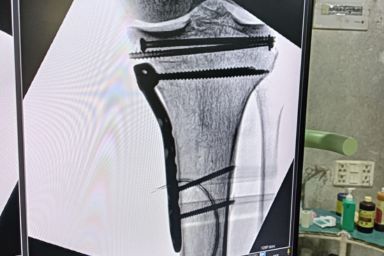

Advanced Orthopaedic Care with Modern OT Facilities by Dr S R Panda

Dr S R Panda is a reputed orthopaedic surgeon in Kolkata offering advanced facilities including General & Joint Replacement OT, Arthroscopy & Trauma OT, and Spine Surgery & Sports Injury OT, ensuring precise diagnosis, modern surgical techniques, and comprehensive bone and joint care under one roof.

General & Joint Replacement OT

Arthroscopy & Trauma OT